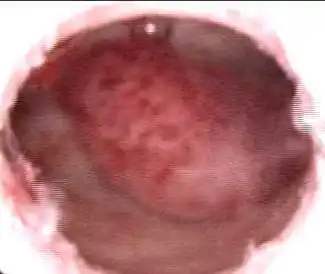

【科普】子宫内膜息肉什么鬼?

子宫内膜息肉